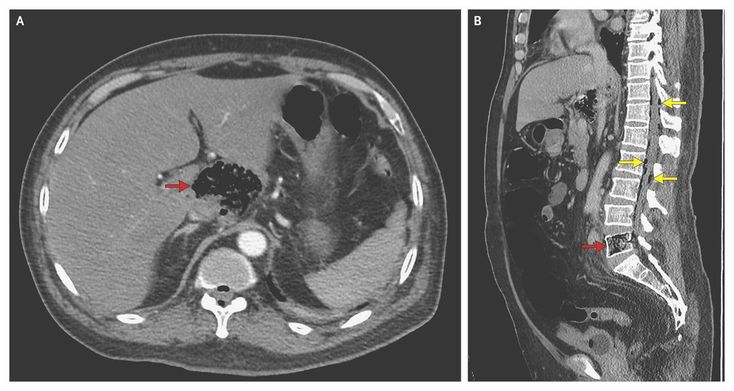

A 60-year-old man of Burmese origin presented to the emergency department with severe back pain that had lasted 1 week. He had a fever (39.8°C) and hyperglycemia but had not received a diagnosis of diabetes previously. He had not traveled to Myanmar (Burma) or been in contact with anyone from Myanmar during the previous 2.5 years. Encephalopathy and multiple organ failure rapidly developed. Computed tomography of the abdomen revealed a gas-forming infection in the caudate lobe of the liver (Panel A, arrow) and the fifth lumbar vertebral body (Panel B, red arrow). Gas extended posteriorly into the epidural space (Panel B, yellow arrows), as well as anterolaterally, particularly along the margin of the right psoas muscle. An abscess in the lower lobe of the right lung was also noted. Cultures of bronchoalveolar-lavage fluid, blood, and material from percutaneous drainage of the liver abscess all grew Klebsiella pneumoniae. The syndrome of primary liver abscess caused by K. pneumoniae infection with septicemia is well recognized, particularly in Taiwan and Southeast Asia. It can be associated with gas formation and metastatic infection. This patient was treated with antibiotic agents and recovered, although damage to his fifth lumbar vertebra had occurred, resulting in chronic back pain.